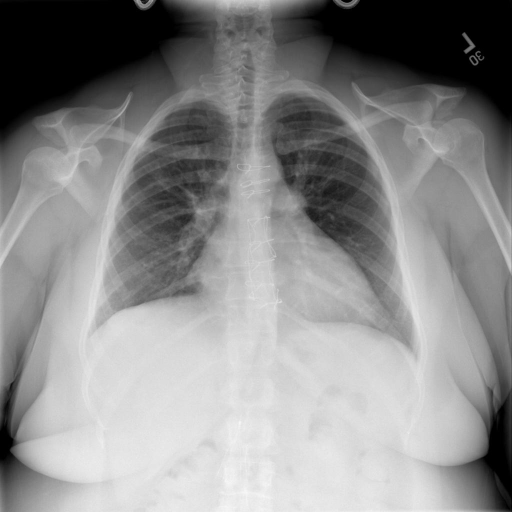

# 本文贡献  - 借助ChatGPT以及公开的数据集,我们构造了一个`X光影像-诊断报告`对的医学多模态数据集; # 数据集 - [MIMIC-CXR](https://physionet.org/content/mimic-cxr-jpg/2.0.0/)是一个公开可用的胸部X光片数据集,包括377,110张图像和227,827个相关报告。 - [OpenI](https://openi.nlm.nih.gov/faq#collection)是一个来自印第安纳大学医院的胸部X光片数据集,包括6,459张图像和3,955个报告。 在上述工作中,报告信息都为非结构化的,不利于科学研究。为了生成合理的医学报告,我们对两个数据集进行了预处理,并最终得到了可以用于训练的**英文报告**。除此之外,为了更好的支持中文社区发展,借助ChatGPT的能力,我们将英文报告进行了中文翻译,并最终形成了可用于训练的数据集。 |数据集|数量|下载链接| |:-|:-|:-| |MIMIC-CXR-zh|-|-| |OpenI-zh|6,423|[诊疗报告](./data/Xray/openi-zh.json) 、[X光影像](https://pan.baidu.com/s/13GBsDMKf6xBZBSHpoWH_EA?pwd=k9sh)| # 快速上手 1. 安装环境 ```bash # 安装依赖 pip install -r requirements.txt # 国内换源安装依赖 pip install -i https://mirrors.aliyun.com/pypi/simple/ -r requirements.txt ``` 此时默认会安装`deepspeed`库(支持`sat`库训练),此库对于模型推理并非必要,同时部分`Windows`环境安装此库时会遇到问题。 如果想绕过`deepspeed`安装,我们可以将命令改为: ```bash # 安装依赖 pip install -i https://mirrors.aliyun.com/pypi/simple/ -r requirements_wo_ds.txt # 安装SwissArmyTransformer pip install -i https://mirrors.aliyun.com/pypi/simple/ --no-deps "SwissArmyTransformer>=0.3.6" ``` 2. 模型推理 # 效果展示 |X光影像|诊疗报告(医生)|XrayGLM| |:-|:-|:-| ||根据X射线图像,心脏大小正常,肺部看起来很清晰。已经排除了肺炎、积液、水肿、气胸、腺病、结节或肿块的存在。该发现表明一切正常。换句话说,总体印象是胸部正常。|X光片显示,心脏大小正常。肺部没有气胸或胸腔积液的证据。骨骼结构看起来没有任何异常。总的来说,X光片表明没有发现急性心肺疾病的迹象。| # 项目致谢 1. [VisualGLM-6B](https://github.com/THUDM/VisualGLM-6B)为我们提供了基础的代码参考和实现; 2. [MiniGPT-4](https://github.com/Vision-CAIR/MiniGPT-4)为我们这个项目提供了研发思路; 3. ChatGPT生成了高质量的中文版X光检查报告以支持XrayGLM训练; 4. [gpt_academic](https://github.com/binary-husky/gpt_academic)为文档翻译提供了多线程加速; 5. [MedCLIP](https://github.com/RyanWangZf/MedCLIP) 、[BLIP2](https://huggingface.co/docs/transformers/main/model_doc/blip-2) 、[XrayGPT](https://github.com/mbzuai-oryx/XrayGPT) 等工作也有重大的参考意义;  这项工作由[澳门理工大学应用科学学院](https://www.mpu.edu.mo/esca/zh/index.php)硕士生[王荣胜](https://github.com/WangRongsheng) 、[段耀菲](https://github.com/IsBaSO4) 、[李俊蓉](https://github.com/lijunrong0815)完成,同时这项工作受到[檀韬](https://scholar.google.com/citations?hl=zh-CN&user=lLg3WRkAAAAJ)副教授、[彭祥佑](http://www.patrickpang.net/)老师的帮助支持。 *特别鸣谢:[USTC-PhD Yongle Luo](https://github.com/kaixindelele) 提供了有3000美金的OpenAI账号,帮助我们完成大量的X光报告翻译工作 # 免责声明 本项目相关资源仅供学术研究之用,严禁用于商业用途。使用涉及第三方代码的部分时,请严格遵循相应的开源协议。模型生成的内容受模型计算、随机性和量化精度损失等因素影响,本项目无法对其准确性作出保证。即使本项目模型输出符合医学事实,也不能被用作实际医学诊断的依据。对于模型输出的任何内容,本项目不承担任何法律责任,亦不对因使用相关资源和输出结果而可能产生的任何损失承担责任。 # 项目引用 如果你使用了本项目的模型,数据或者代码,请声明引用: ```bash @misc{wang2023XrayGLM, title={XrayGLM: The first Chinese Medical Multimodal Model that Chest Radiographs Summarization}, author={Rongsheng Wang, Yaofei Duan, Junrong Li, Patrick Pang and Tao Tan}, year={2023}, publisher = {GitHub}, journal = {GitHub repository}, howpublished = {\url{https://github.com/WangRongsheng/XrayGLM}}, } ``` # 使用许可 此存储库遵循[CC BY-NC-SA](https://creativecommons.org/licenses/by-nc-sa/4.0/) ,请参阅许可条款。